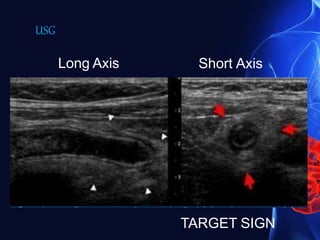

Sign of acute appendicitis in ultrasound

• Blind-ending tubular structure at the point of tenderness

• Non-compressible

• Diameter 7 mm or greater

• No peristalsis

• Appendicolith casting acoustic shadow

• High echogenicity non-compressible surrounding fat

• Surrounding fluid or abscess

• Oedema of caecal pole

• Hypervascularity on power Doppler

Long Axis Short Axis

TARGET SIGN

USG

Ultrasound images showing an anechoic blind-ending tubular structure

measuring 10mm in diameter in the right iliac fossa (RIF): this was

found to be non-peristaltic and non- compressible.

An echogenic round body, with posterior acoustic shadowing seen

within the tubular structure, in keeping with an Appendicolith.